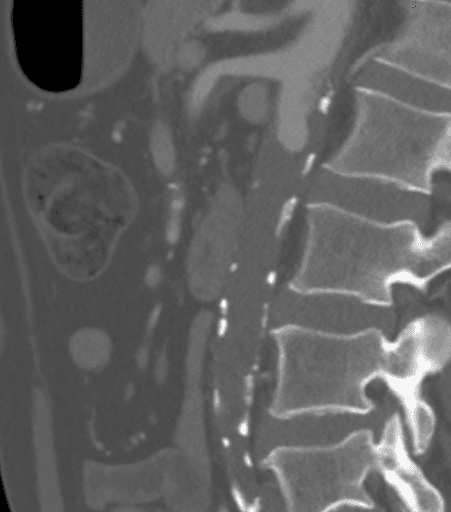

La CTA ha dimostrato un'occlusione aortica completa a livello delle arterie renali bilaterali da una combinazione di placca aterosclerotica calcificata e morbida. In modo significativo, in questo caso, l'ateroma si estendeva prossimalmente fino al livello dell'arteria mesenterica superiore (SMA), come visto nella Figura 1, il che avrebbe complicato il clamping suprarenale e compromesso l'afflusso appropriato per il bypass aortofemorale standard (AFB). L'aorta supraceliaca era priva di malattie arteriose (Figura 2). L'occlusione si estese alle arterie femorali comuni bilaterali, dove il flusso veniva ricostituito dalle arterie collaterali epigastriche e circonflesse iliache. Le arterie femorali comuni bilaterali (CFA) presentavano una placca ateromatosa di circa il 60% di stenosi, e poi il deflusso era intatto sotto la biforcazione della CFA.

Figura 2. La CTA ha mostrato che l'aorta supraceliaca era priva di malattia arteriosa.